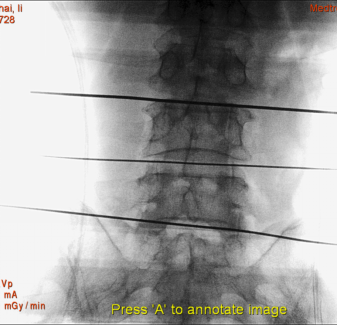

(1)患者采用俯卧位,提前设置好O型臂多维外科成像系统所需扫描定位平面(图1,图2),在正位透视下标定一条腰椎棘突中线,再沿髂棘最高点做一水平线,腰5骶1椎间盘正侧位的透视交叉点,即为穿刺点,一般在中心线旁开10-12cm左右处选一穿刺点。此线为穿刺的方向和角度(图3)。

图1 定位椎间隙 正位